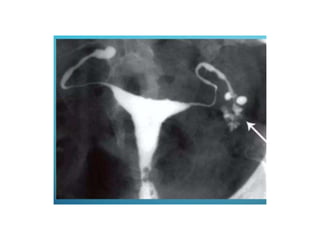

• Hydrosalpinx

• Common cause- salpingitis

• Distal tubal occlusion- dilatation of proximal

segment

• Hydrosalpinx • Commoncause- salpingitis • Distal tubal occlusion- dilatation of proximal segment